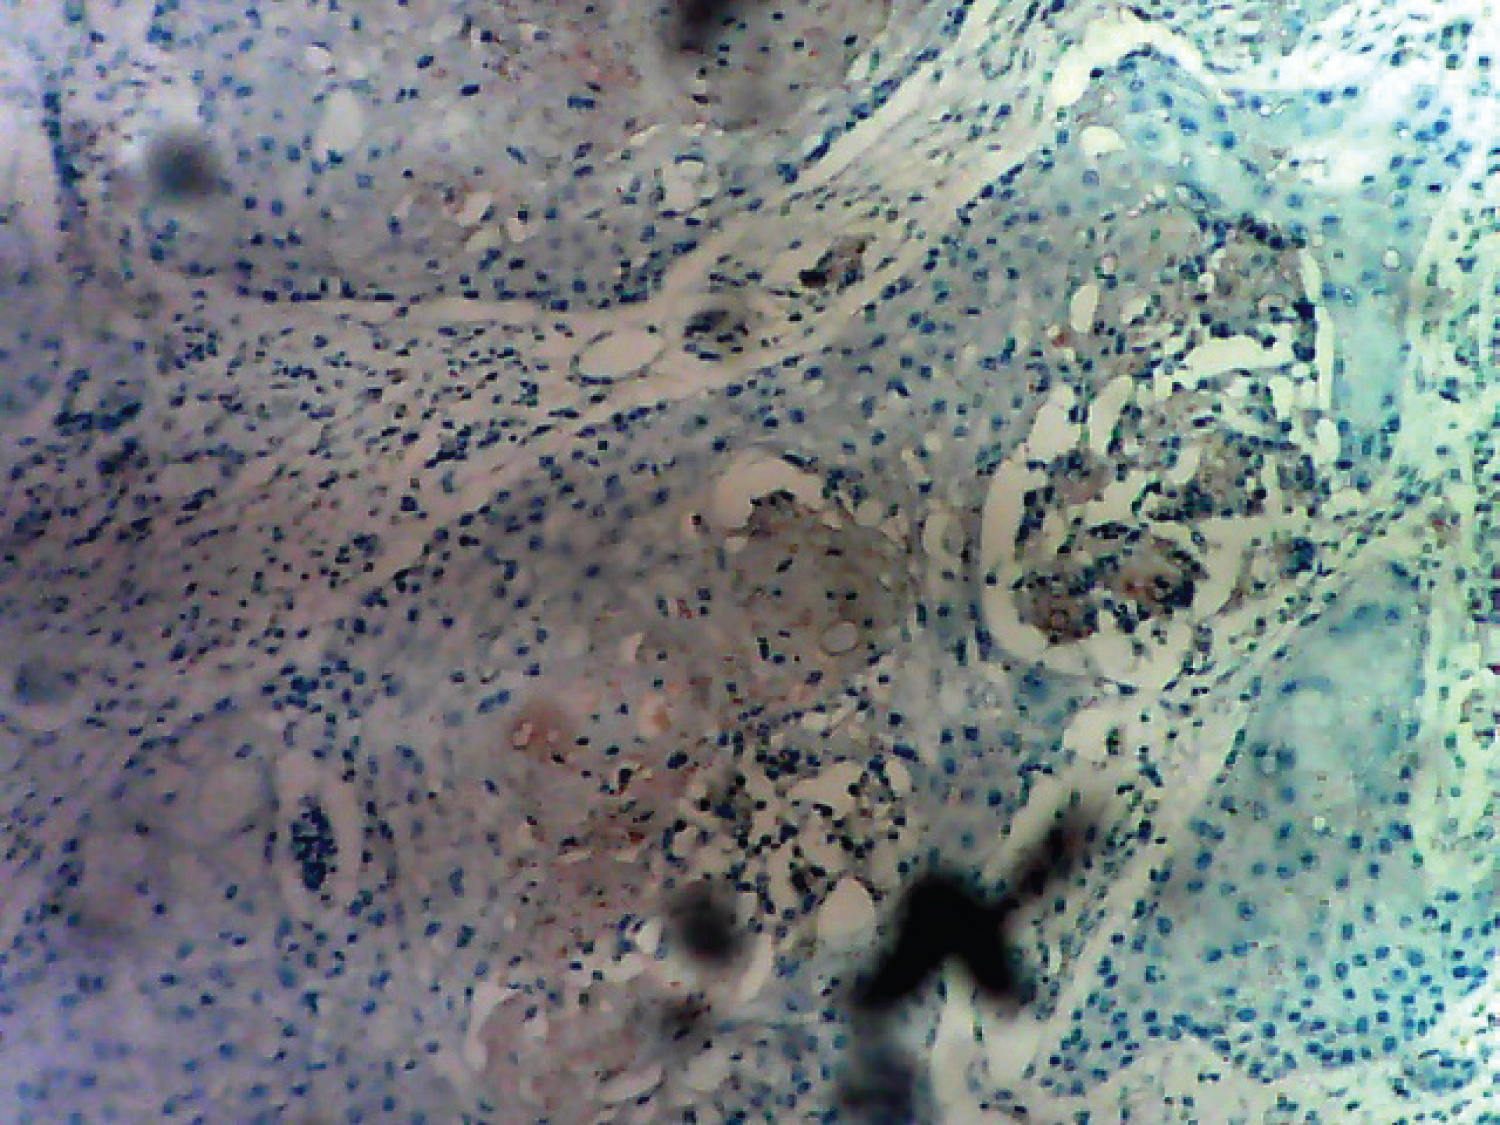

Microscopically, histologic sections of the tumour show infiltration by malignant squamous epithelial cells that are disposed in cell nests. The cells are large and pleomorphic with glassy appearance. They have vesicular nuclei and scanty cytoplasm. They show individual cell keratinization and intercellular bridges with areas of intratumoural infiltration by mononuclear inflammatory cells, comprising lymphocytes and plasma cells. Keratin pearls and areas of dystrophic calcification are seen. No ductal or glandular element is seen. The overlying skin is unremarkable (Figure 1, Figure 2 and Figure 3). The overall features are in keeping with pure squamous cell carcinoma of the breast (large cell keratinizing variant). The resection margins and the axillary lymph nodes are free of the malignant cells. Immunohistochemical staining of the tumour cells are negative for ER, PR and HER2/neu but are strongly positive for CK5/6 (Figure 4, Figure 5, Figure 6 and Figure 7).

Figure 4: Tumour cells showing cytokeratin (CK) 5 and 6 positivity. View Figure 4

Figure 5: Tumour cells showing estrogen receptor ER negativity. View Figure 5

Figure 6: Tumour cells showing progesterone receptor PR negativity. View Figure 6

Figure 7: Tumour cells negative for HER2/neu. View Figure 7

Most cases of PSCC of the breast do not show hormonal (oestrogen, progesterone and HER-2/neu) expression. The oestrogen ER and progesterone PR receptor expression are negative in more than 90% of the cases [5,7,8,10,11]. This is consistent with our finding in this case as ER, PR and HER2/neu are all negative while CK5/6 is strongly positive. In the literature, only 4 cases of HER-2/neu over-expression in PSCC of the breast have been reported in the literature. One case was reported by Karamouzis, et al. [12] while in a series reported by Shui, et al. in Shanghai, China; 3 cases of HER-2/neu over expression was reported out of 30 cases of PSCC of the breast [13]. Most cases of PSCC of the breast are characterized by lack of micro calcification on mammogram. In the literature, there are 2 reported cases of SCCB that show micro calcifications on mammogram [14,15]. The case we report did not do mammography, although areas of calcification are seen in histological sections.